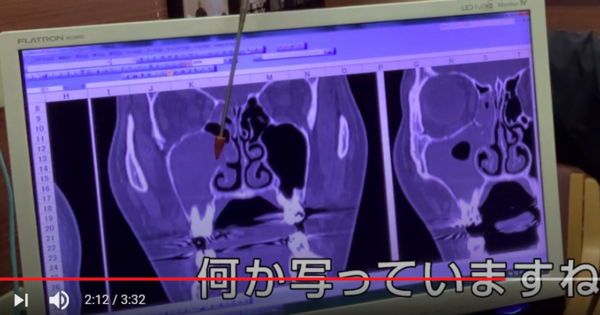

指している

空気がないといけないところに

何かうつっていますね?

何かが鼻の中にある

というところですね。

副鼻腔

上顎洞の中の場所になりますので

副鼻腔炎

という病名がつきます。

もっと見てみると

少し歯の根っこが

鼻の部屋に入り込もうとしています。